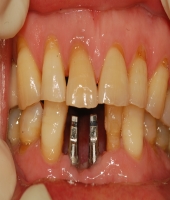

| ● 진료과목 : [임플란트] 하악 전치부 골폭이 좁은 경우

| ● 내용 : 일체형 임플란트로 . . |